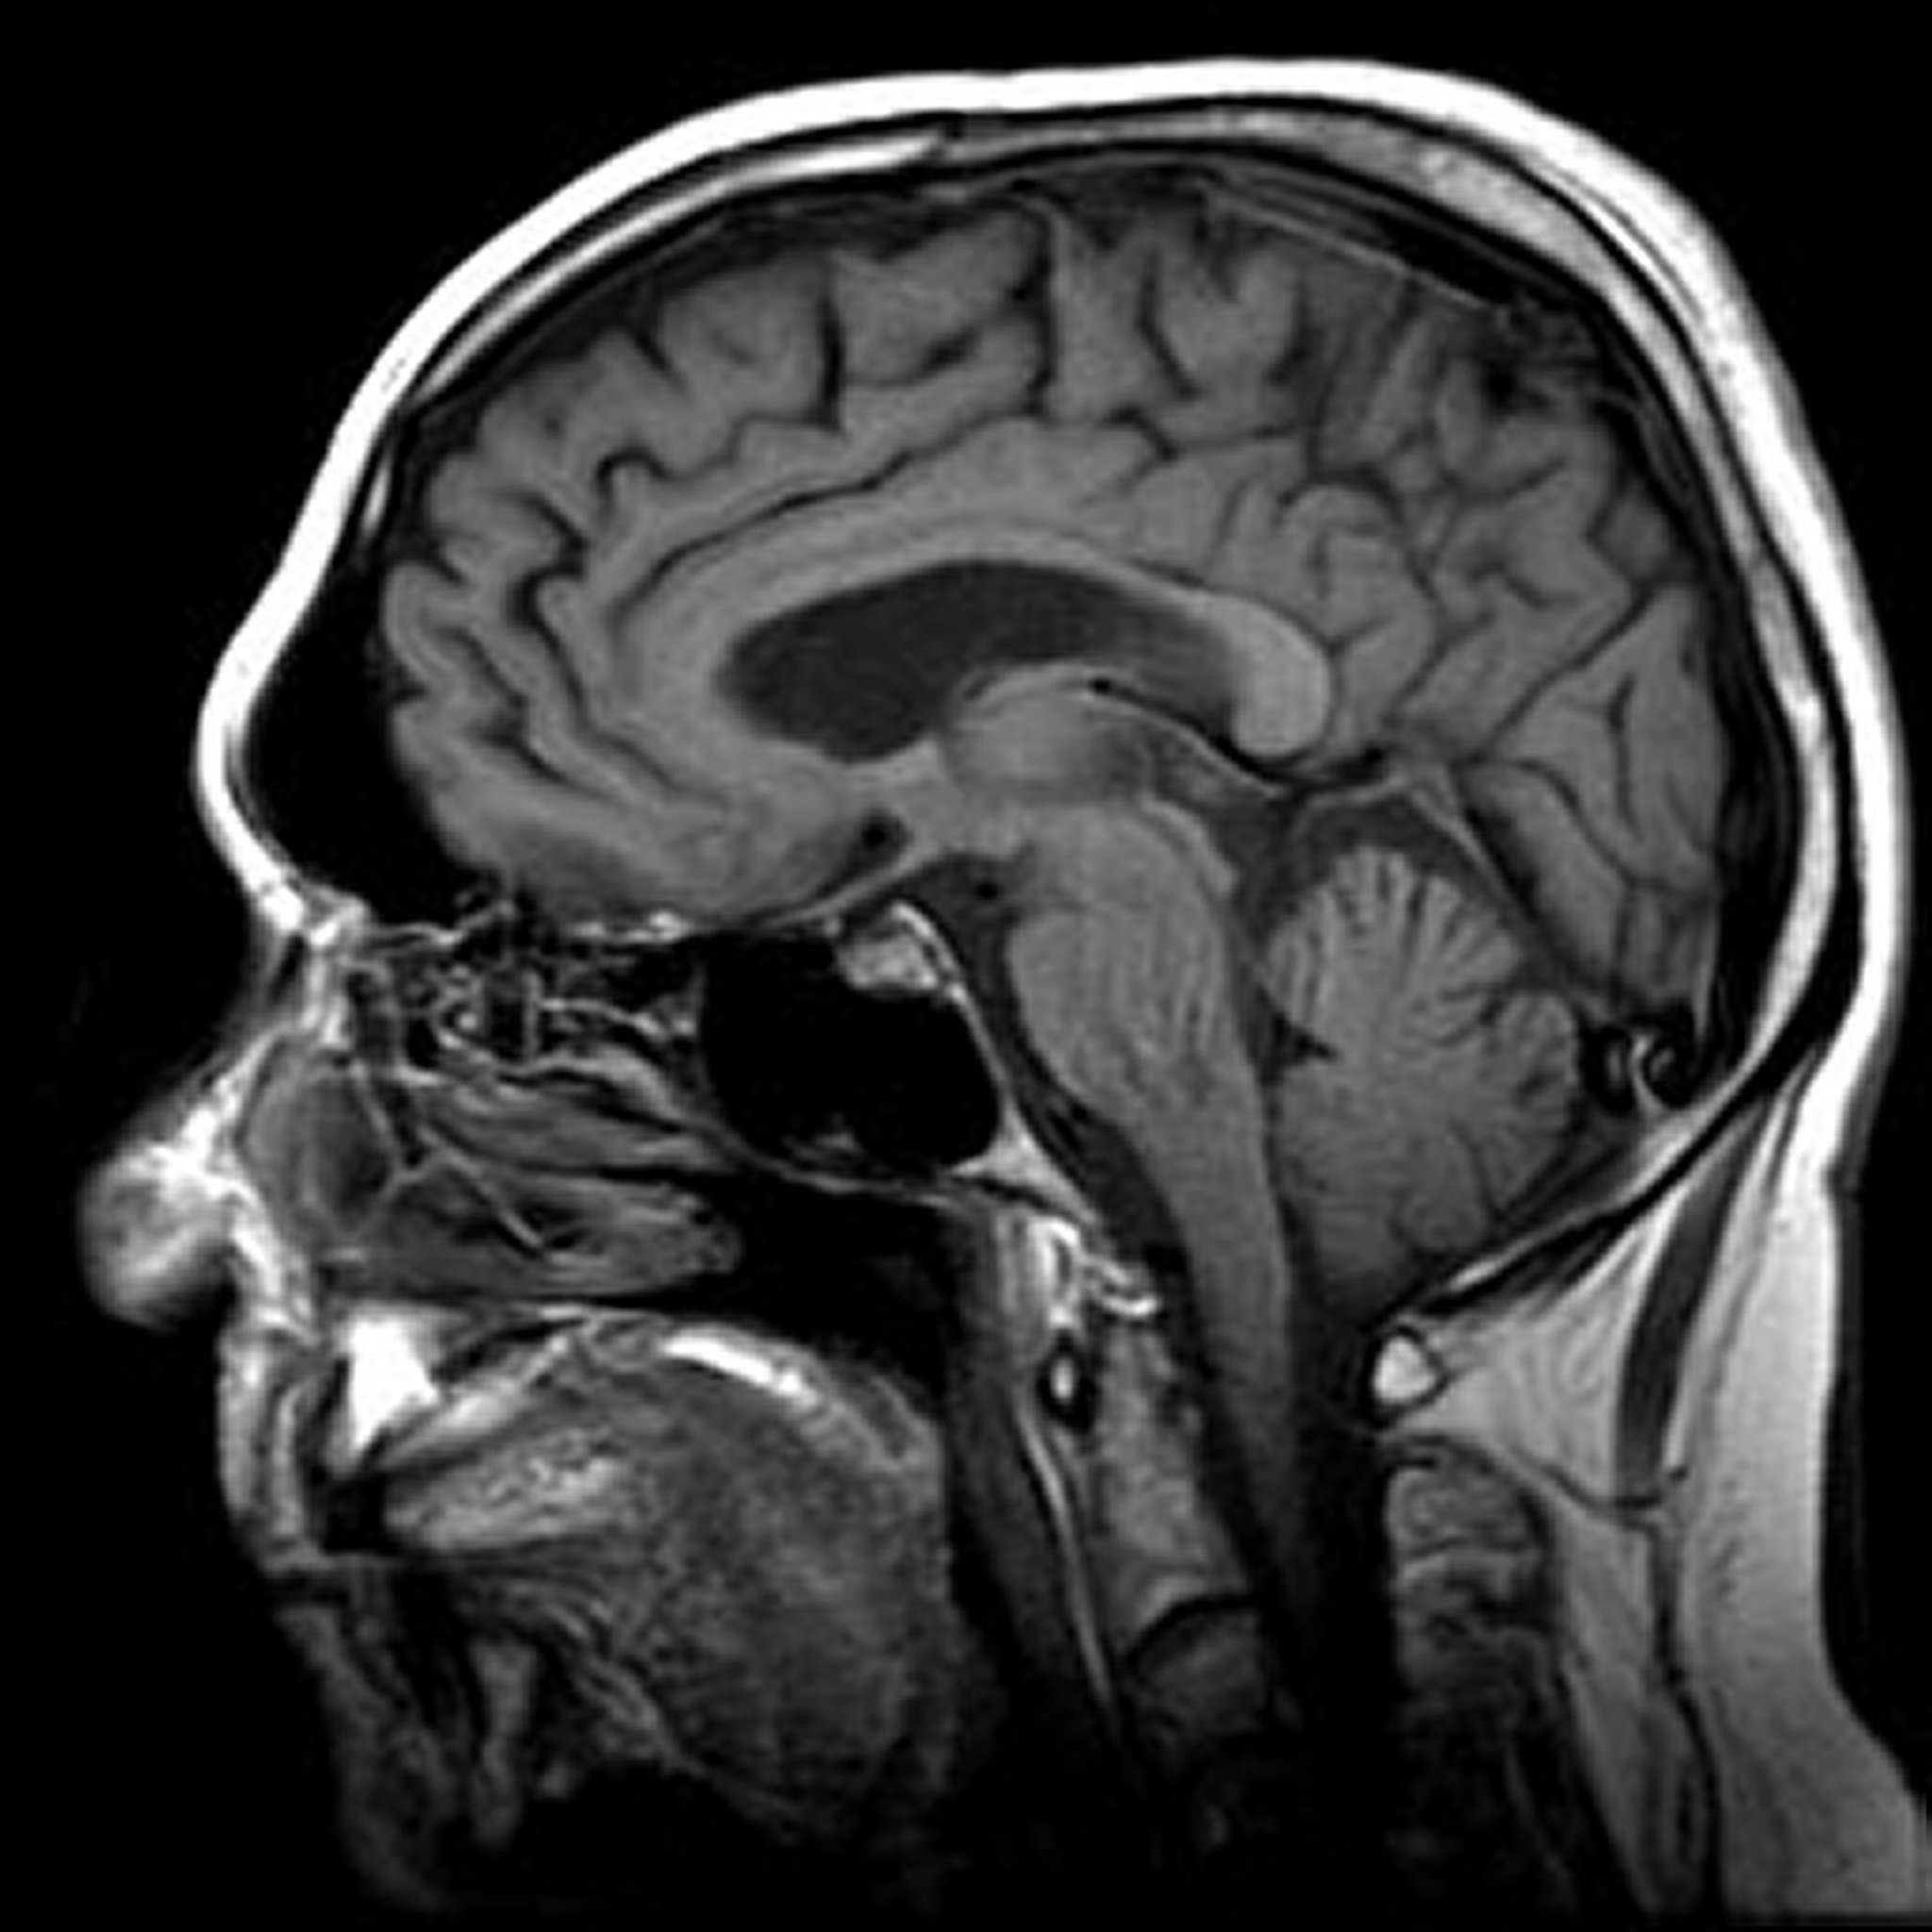

Gambar disediakan oleh Jon A. Jacobson, MD.

MRI lebih disukai daripada tomografi terkomputasi (CT) ketika dokter membutuhkan lebih banyak detail tentang jaringan lunak—misalnya, untuk menggambarkan abnormalitas di otak, sumsum tulang belakang, otot, dan hati. MRI sangat berguna untuk mengidentifikasi tumor pada jaringan ini.

MRI Fungsional mendeteksi perubahan metabolik yang terjadi saat otak aktif. Dengan demikian, dapat menunjukkan area otak mana yang aktif ketika seseorang melakukan tugas tertentu, seperti membaca, menulis, mengingat, menghitung, atau menggerakkan anggota tubuh. MRI Fungsional dapat digunakan dalam penelitian dan pengaturan klinis, misalnya untuk merencanakan bedah epilepsi otak.